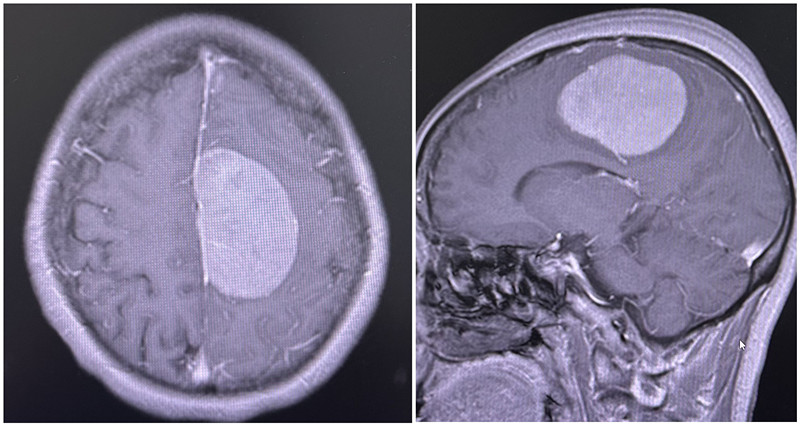

2024年10月,梁女士因左侧肢体麻木及行动不便在外院检查,头颅核磁共振结果提示左侧顶部占位性病变,性质不明。为求进一步诊治,她来到我院神经外科门诊。经神经外科首席专家李松年主任医师详细检查,考虑为左侧大脑镰旁脑膜瘤,更棘手的是,术前影像显示肿瘤与周围血管、功能区脑组织存关系密切。

大脑镰旁区域血管丰富、解剖结构复杂,手术既要完整切除肿瘤,又要避免损伤周围正常血管和神经组织,否则可能引发大出血、肢体功能障碍等严重并发症,对术者的技术精准度和操作稳定性提出了极高要求。

患者术前核磁共振影像